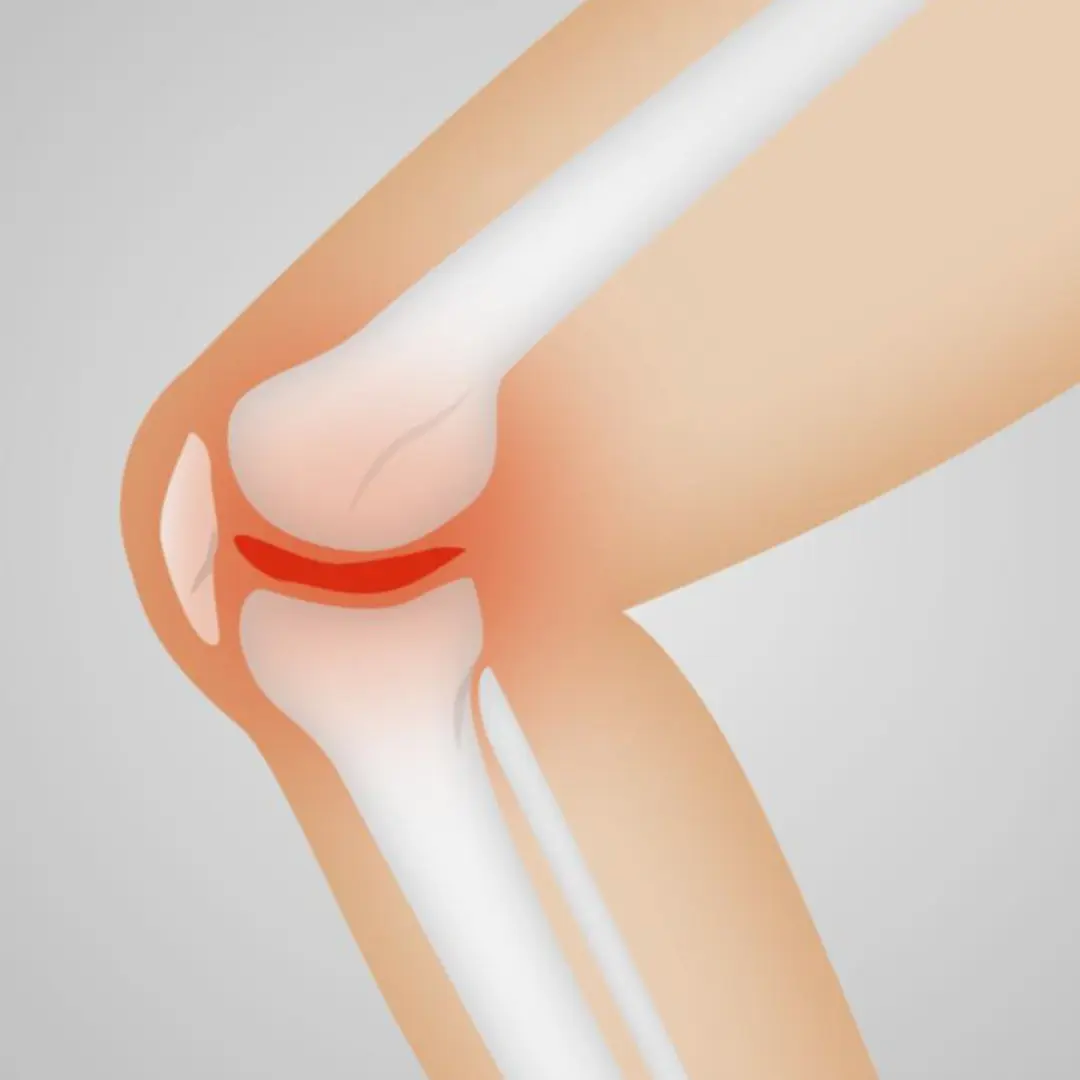

- 가장 흔한 원인 중 하나로, 나이가 들면서 무릎 관절의 연골이 점차 닳아 없어지는 현상입니다. 연골은 뼈의 마찰을 줄여주는 역할을 하는데, 연골이 닳으면 뼈와 뼈가 직접 부딪히면서 통증과 염증을 유발합니다.

- 퇴행성 관절염: 가장 흔한 무릎 통증의 원인입니다. 나이가 들면서 무릎 관절의 연골이 점차 닳아 없어지는 질환으로, 뼈와 뼈가 직접 마찰하면서 통증, 뻣뻣함, 부종 등을 유발합니다. 주로 아침에 뻣뻣하고 움직일 때 통증이 심해지는 특징이 있어요.

- 반월상 연골판 손상: 무릎 관절 사이에 있는 C자 모양의 연골판이 찢어지거나 손상되는 질환입니다. 스포츠 활동 중 발생하기 쉽고, 쪼그려 앉거나 무릎을 비트는 동작에서 통증이 심해지며, 무릎이 펴지지 않는 '잠김 현상'이 나타날 수 있습니다.

- 슬개골 연골연화증: 무릎뼈(슬개골) 뒤쪽 연골이 물렁해지면서 통증을 유발하는 질환입니다. 특히 계단을 오르내리거나 앉았다 일어설 때, 무릎을 굽히고 있을 때 통증이 심해지는 경향이 있어요. 주로 젊은 여성이나 운동선수에게 많이 나타납니다.